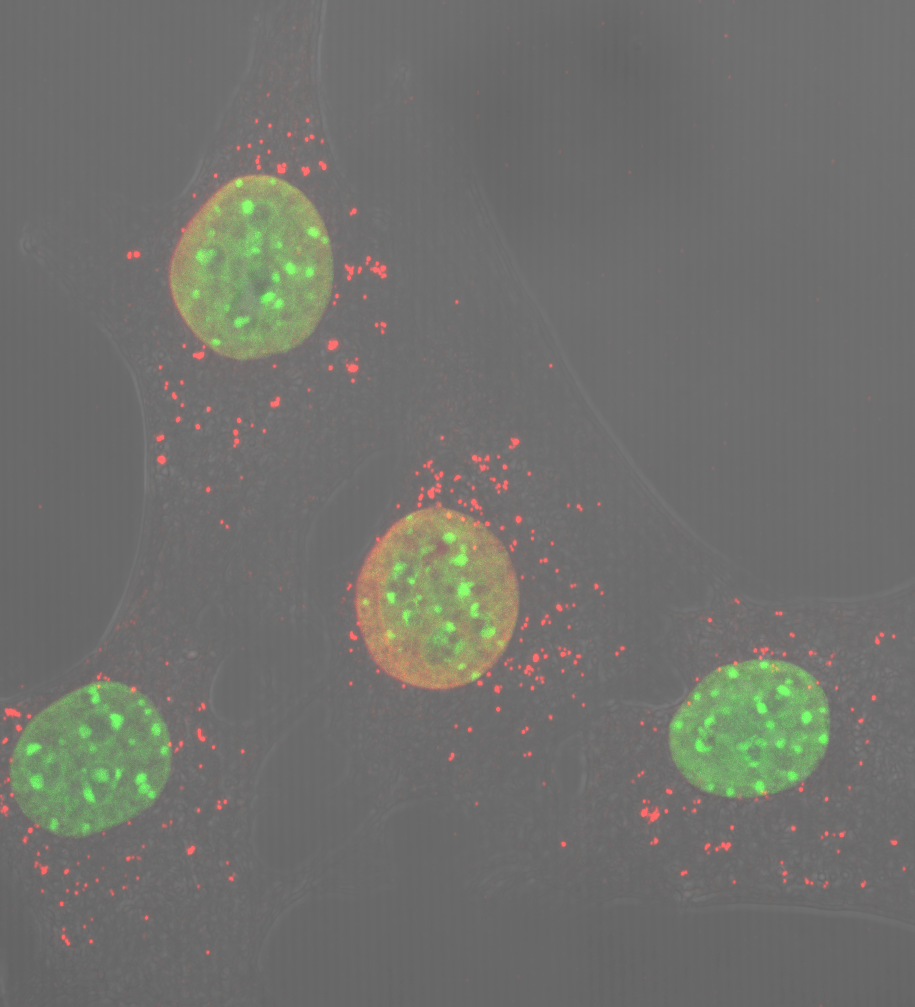

• CIBERDEM

La falta de una única proteína mitocondrial genera inflamación severa

10/04/2018